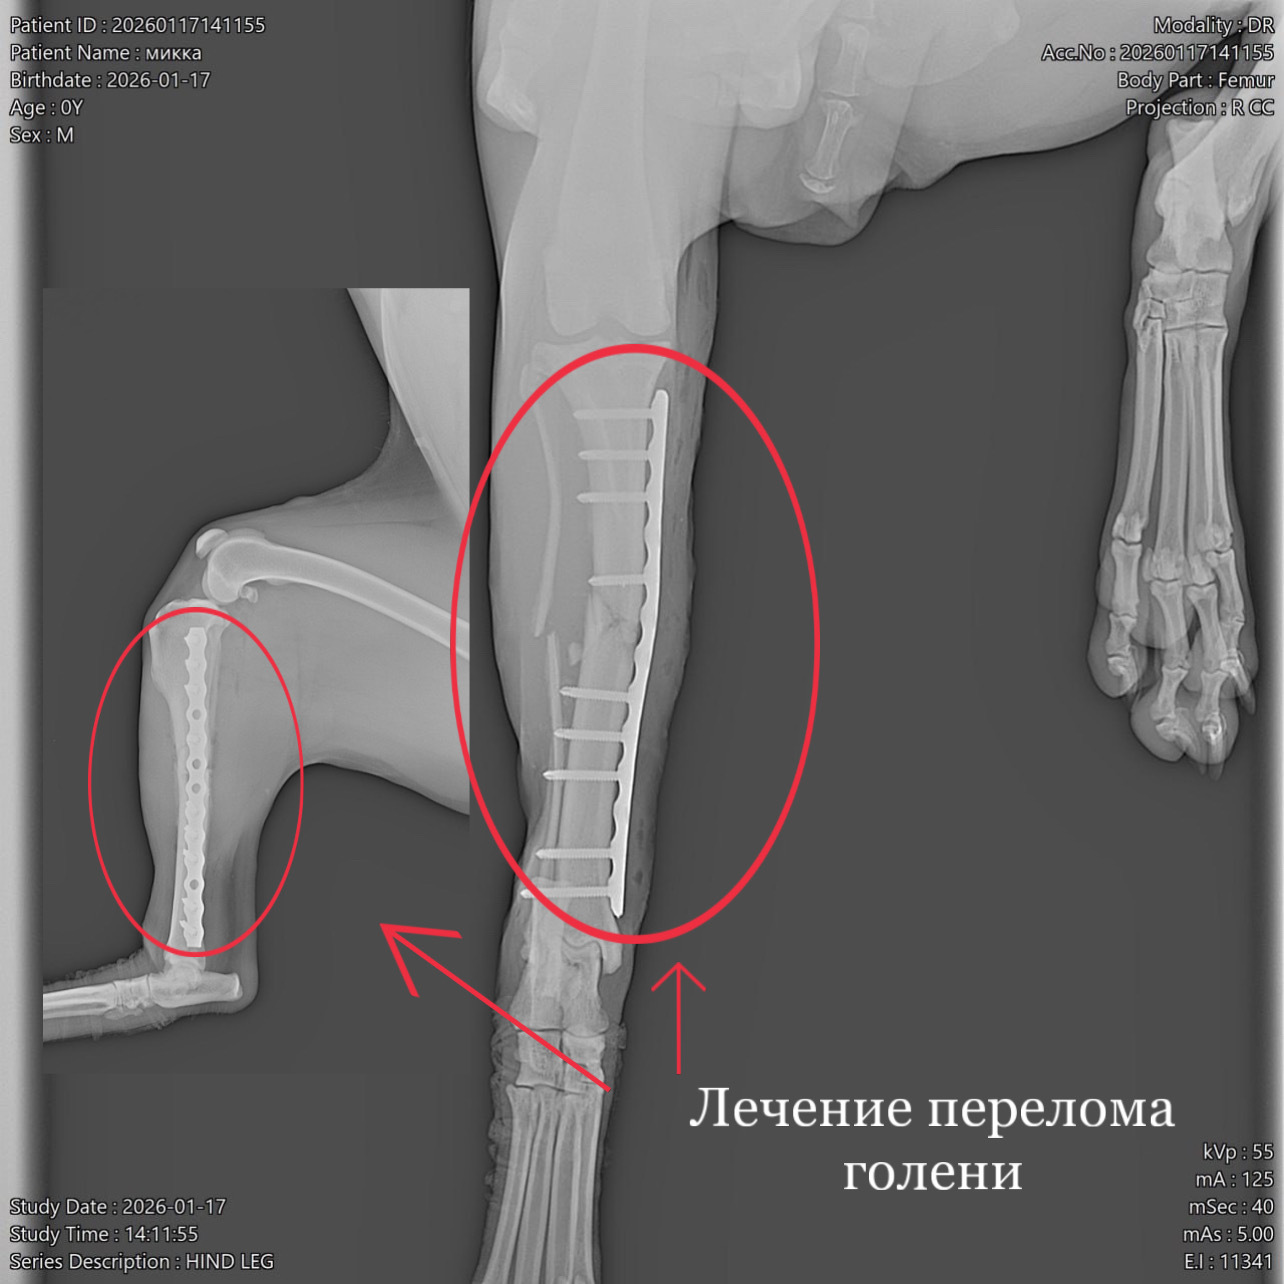

Кане-корсо. Поперечный перелом голени со смещением

В клинику обратилась собака породы кане-корсо (2 года). Со слов владельцев животное убежало из дома на 11 дней, вернулась с висячей конечностью, в течении 3 дней владельцы искали клинику для проведения операции. По результатам рентгенологического исследования выявлен диафизарный поперечный перелом голени со смещением. По согласованию с владельцами провели металлоостеосинтез трубчатых костей накостной пластиной. В ходе операции было обнаружено образование псевдоартроза (ложного сустава), костные отломки были зачищены и репонированы (сопоставлены) согласно их анатомии. Владельцем были даны послеоперационные рекомендации по уходу за животным.